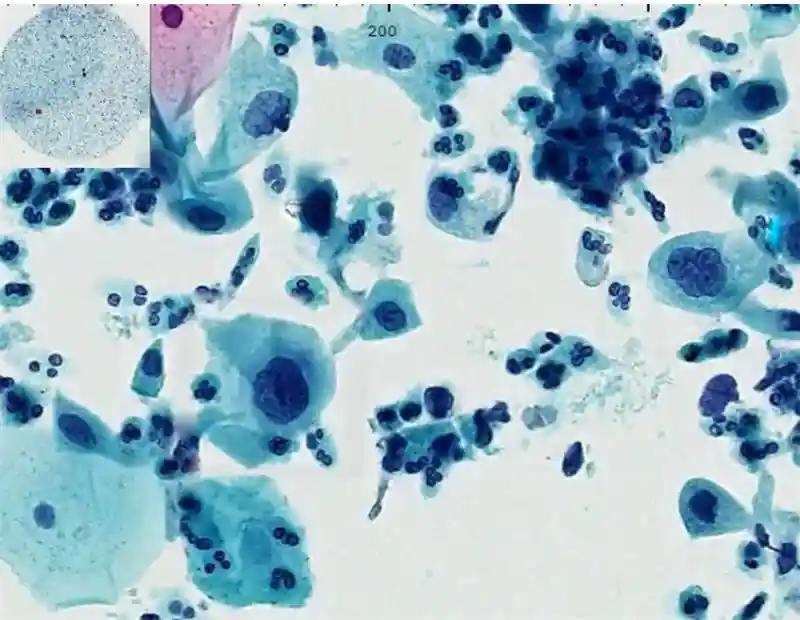

Cervical Image